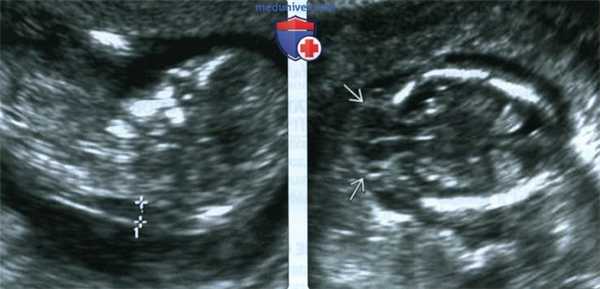

(Слева) ТАУЗИ плода в I триместре. Определяется умеренное утолщение воротникового пространства (кали-перы). По поводу неровных контуров задней части свода черепа выполнено ТВУЗИ.

(Справа) ТВУЗИ подтверждает наличие дефекта задней части свода черепа, а также затылочного энцефалоцеле крупных размеров, содержащее мозжечок целиком. Показан тщательный поиск других пороков развития.